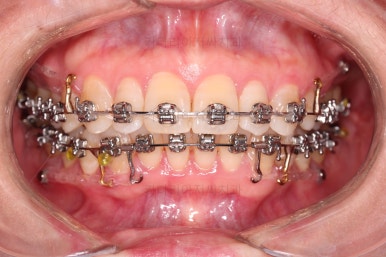

초진 시, 입안의 모습이에요.

"최근 들어 점점 틀어지고, 점점 튀어나오고, 점점 사이가 벌어져요."

이번에 사용하신 장치는 엠파워 메탈이라고 하는 자가결찰 금속 장치인데요.

금속 재료를 시각적으로 신경쓰지 않으셔꼬 메탈장치가 세라믹에 비해 양치라던지 잇몸에 그래도 약간의 장점이 있어서 추천되기도 했어요.

위 사진에서도 어금니쪽 잇몸 부위를 보시면 아주 작은 금속성 나사머리가 보이실건데요. 나사로 단단히 지탱해주고 치열을 뒤로 당겨주는 원리죠.